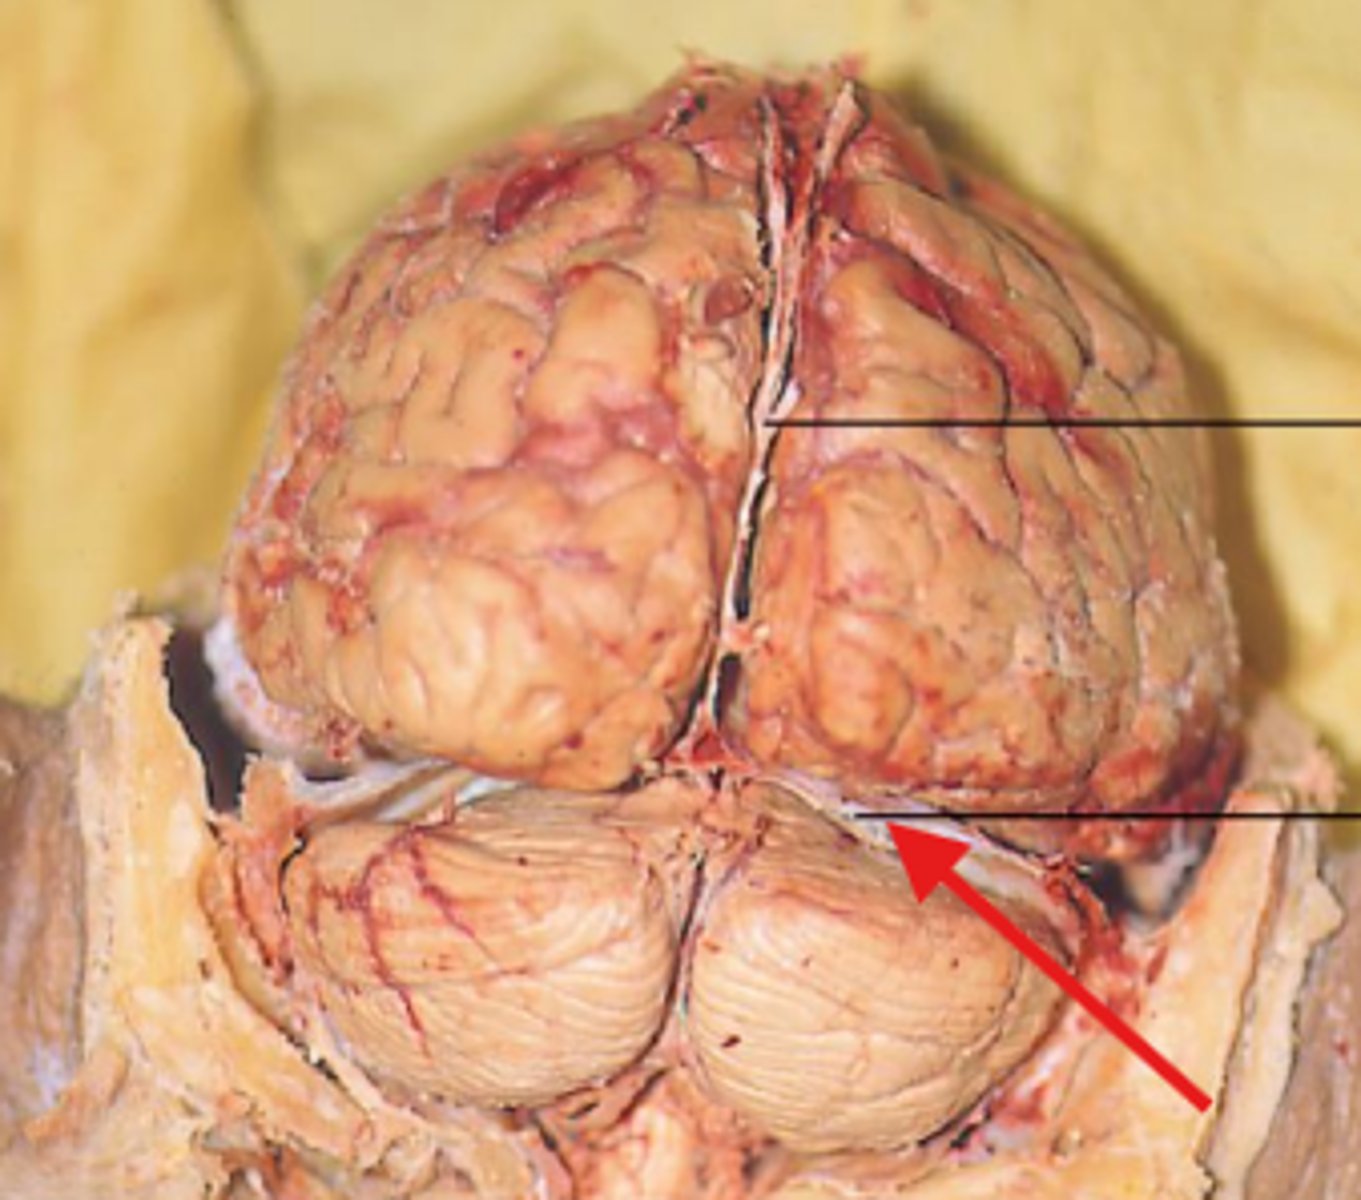

What is the red arrow pointing at?

what structure is the red arrow pointing at?

Red arrow is pointing at what?

What structure is the red arrow pointing to?